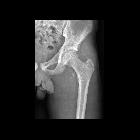

Avulsionsfraktur Trochanter minor

Pelvis and hip

- lesser trochanter: iliopsoas

Many avulsion fractures are apparent of plain radiographs. The avulsed bone fragment is typically displaced in the direction of the tendon, ligament or joint capsule which is attached to it . CT and/or MRI may be required for detection and further characterization. Appearances will vary depending on classification :

- acute: avulsed bone fragment with donor site and typically associated soft tissue swelling / joint effusion